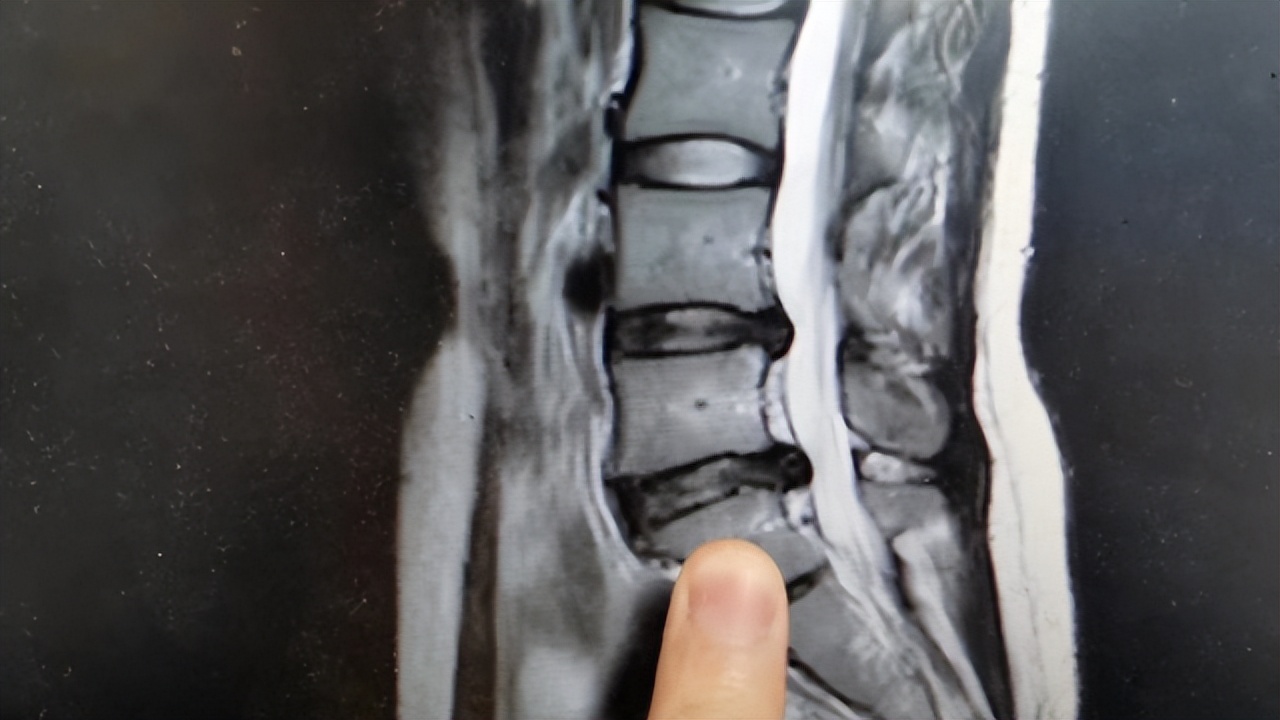

大家口中的“腰突”,其实就是腰椎间盘突出症的简称,它的发生主要和腰椎间的退行性改变、腰椎间盘血液循环能力差、遗传因素等有关。例如若成年人的腰椎间盘血液循环能力差,可能会加重腰椎间盘的承受压力,最终导致髓核的突出。

不容忽视的是,腰椎间盘突出症对身体的影响不小,这也是很多人认定其需要做手术的原因。腰椎间盘突出可能会极大影响患者的脊柱,甚至出现畸形的情况,这就致使多数人会将腰椎间盘突出和手术挂钩,然而事实却和大家的预想不同。